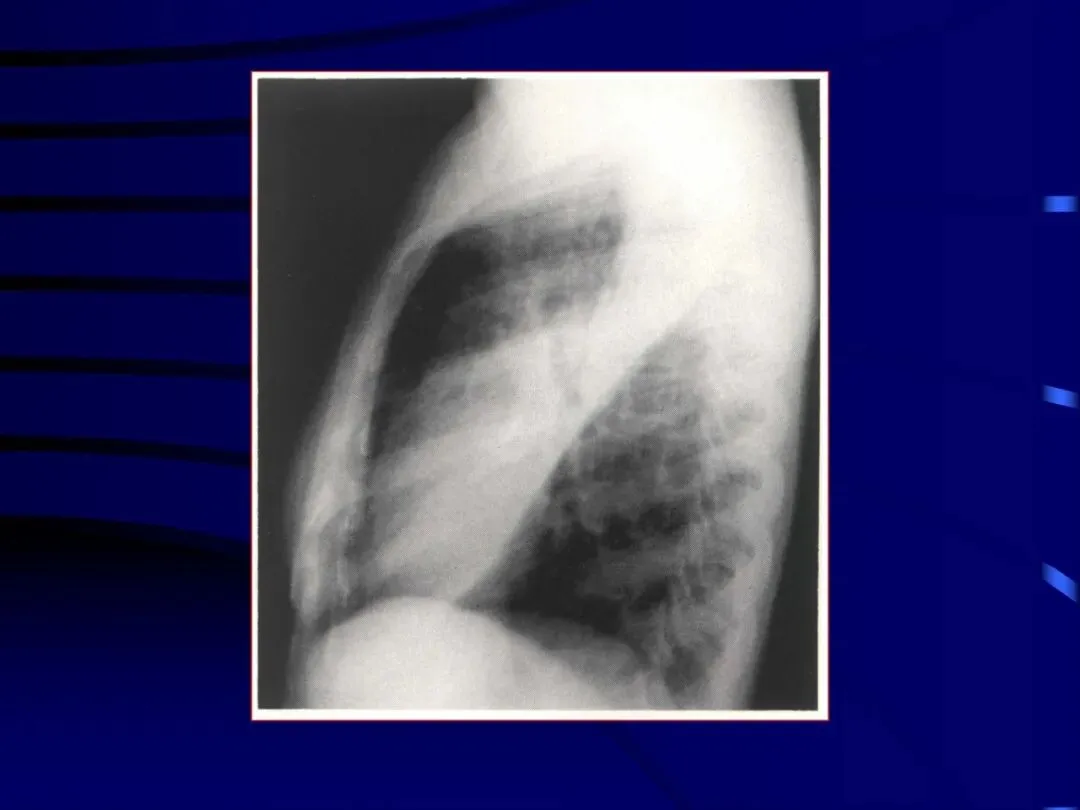

>内科学课件_肺部感染性疾病2-细菌性肺炎

内科学课件_肺部感染性疾病2-细菌性肺炎